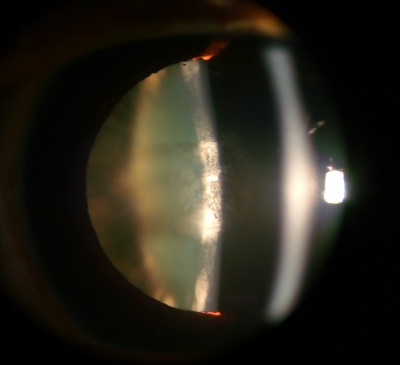

Cortical Cataract

Etiology

Cortical cataracts occur when the portion of lens fibers surrounding the nucleus become opacified. The impact on vision is related to how close the opacities are to the center of the visual axis, and their effect can vary greatly. Progression is variable, with some progressing over years and others in months. The most common symptom of cortical cataract is glare, especially from headlights while night driving.

Symptoms

- Glare often the predominate symptom

- Decreased distance and near vision

- Decreased contrast sensitivity